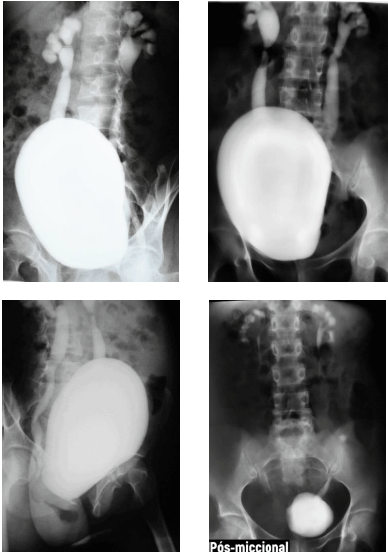

Criança de cinco anos de idade realizou exame contrastado de uretrocistografia miccional, que evidenciou os achados demonstrados nas imagens precedentes.

Acerca dos exames contrastados e das alterações do trato urinário na infância, julgue o próximo item.

Há sinais de estenose das junções ureteropélvicas bilateralmente.

A uretrocistografia miccional, além de identificar a presença de refluxo vesicoureteral, tem a capacidade de avaliar o grau do refluxo, que, no paciente em questão, é classificado como grau II.

Algumas das indicações para a realização de uretrocistografia miccional incluem infecções do trato urinário superior de repetição, pesquisa de alterações sequelares de sondagens vesicais de demora e pesquisa de sequelas de doenças sexualmente transmissíveis em adultos.